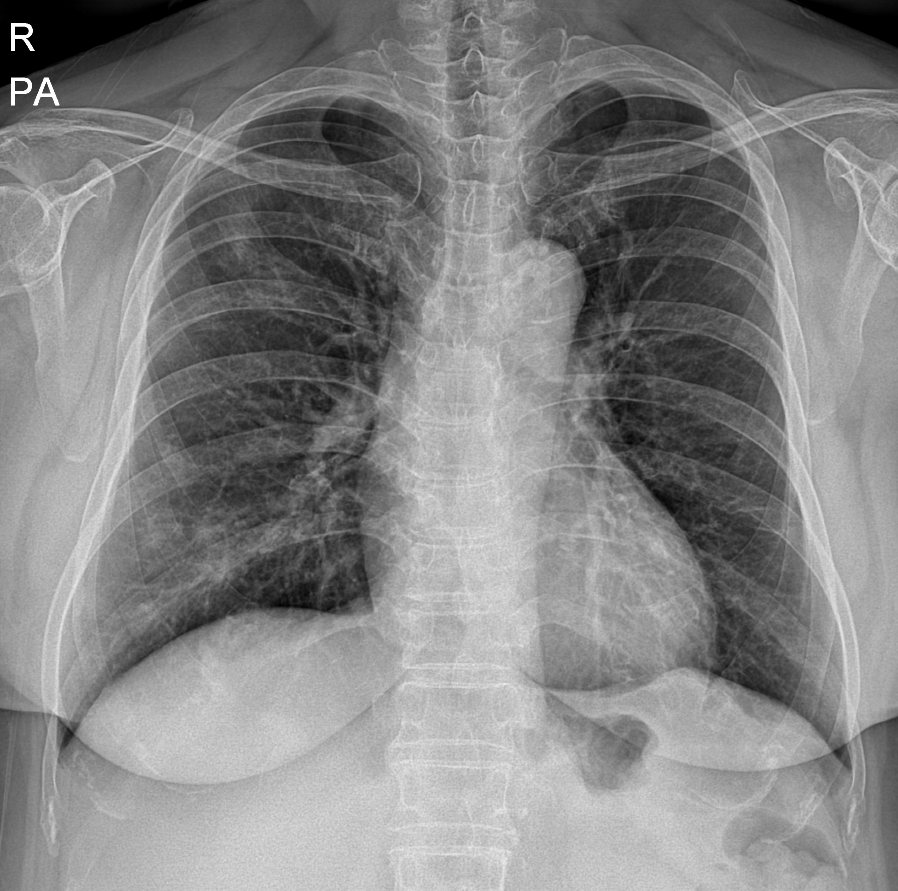

66세 여성

왼쪽부터 우상엽/하엽 폐렴 진단 당시의 흉부 엑스레이, 치료 4일째, 치료 1주째